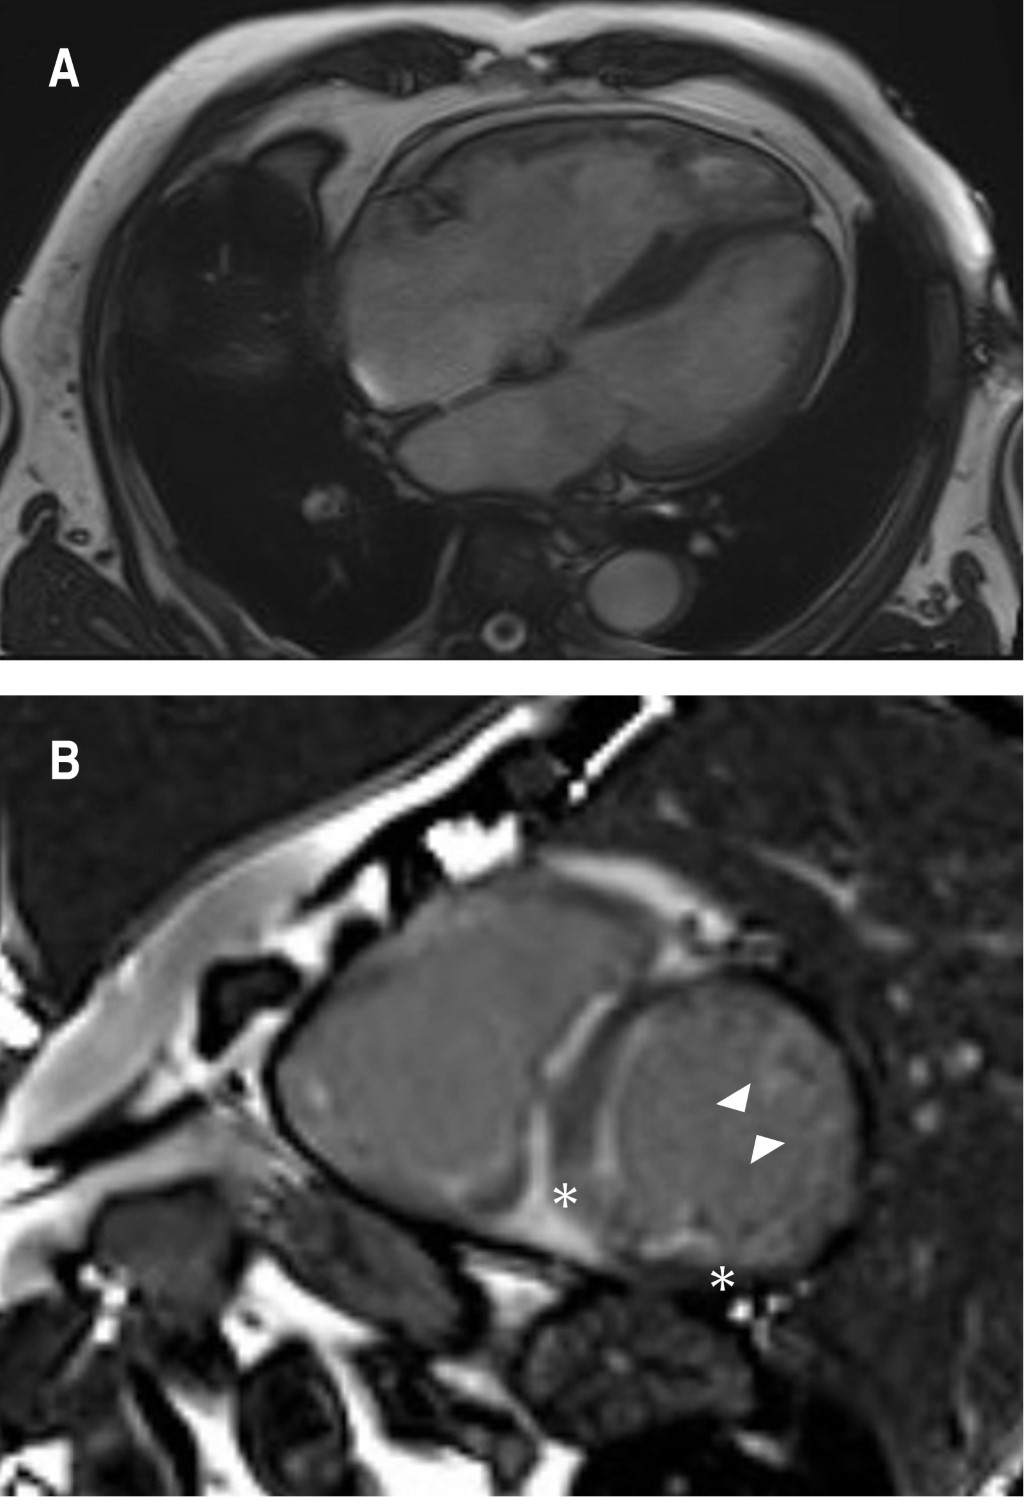

A transthoracic echocardiogram revealed a dilated left ventricle with end-diastolic diameter 60 mm, mild to moderate septal hypertrophy and severely depressed systolic function (20% LVEF by Simpson) due to global hypokinesia. He also had biatrial dilatation, a severely dilated right ventricle with depressed systolic function, mild regurgitation of the four heart valves, mild pulmonary hypertension and dilated inferior cava vein. A cardiovascular magnetic resonance (CMR) showed biventricular dilatation and systolic dysfunction (Figure 1A). High native T1 values (1304 milliseconds) and an increase in extracellular volume (40 with a 43.2% hematocryte) were reported and T1 PSIR sequences disclosed epicardic mid inferolateral, inferoseptal, subendocardial anterior and anterolateral late gadolinium enhancement (Figure 1B). These findings were compatible with infiltrative cardiomyopathy and suggestive of cardiac amyloidosis. At this point, a 99mTc-DPD bone scintigraphy, a blood and urine analysis to evaluate a possible monoclonal component -according to the latest recommendations on the diagnosis of cardiac amyloidosis4 and cardiac catheterization were requested. ATTR cardiomyopathy compatible images were reported in the scintigraphy with a significant Perugini grade 3 heart uptake of the radiotracer (Figure 2). The coronary angiography showed only mild irregularities in the left anterior descending and circumflex coronary arteries without significant obstructive lesions. The search for light chain immunoglobulin monoclonal gammopathy was negative, AL amyloid heart disease was ruled out, so ATTR cardiomyopathy was diagnosed.

Figure 1